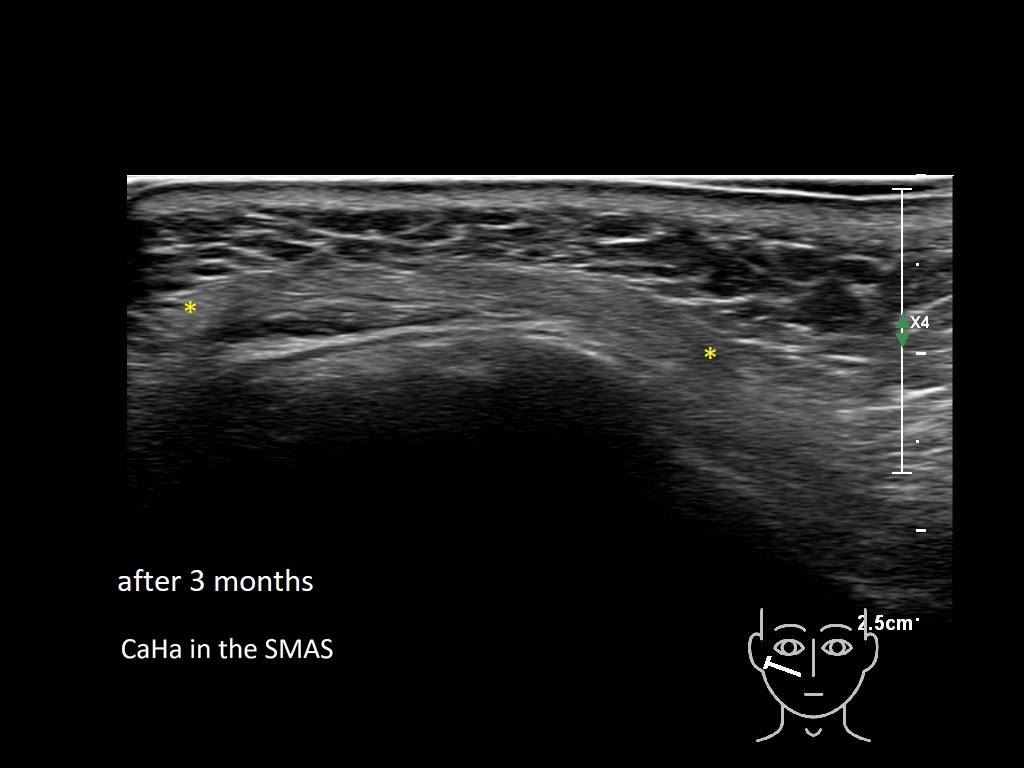

Draw in the image on the right where the fillers are located. To check if your answer is correct, please click on the secondary image.

Draw in the second image below where the fillers are located. To check if your answer is correct, swipe the first image to the right.